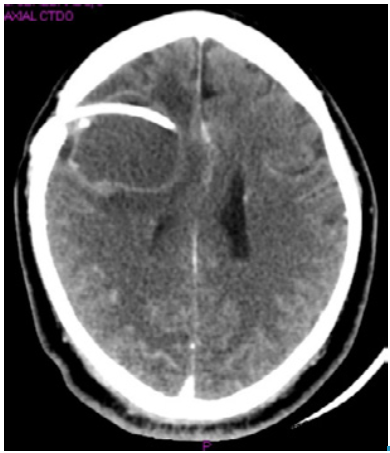

A week after admission, the patient presented with left hemiplegia and sialorrhea, and he did not have any verbal response. A craniotomy was performed to remove the cyst and conduct a histopathological study, while a ventriculoperitoneal shunt was arranged to reduce intracranial pressure (Figure 2). Macroscopically, neurosurgery reported a frontal cyst of greenish content with walls strongly adhered to the parenchyma and the frontal horn of the lateral ventricle. Histopathological analysis confirmed the suspicion of NCC and reported reactive gliosis. The patient evolved satisfactorily, did not present any type of sequelae and was discharged.